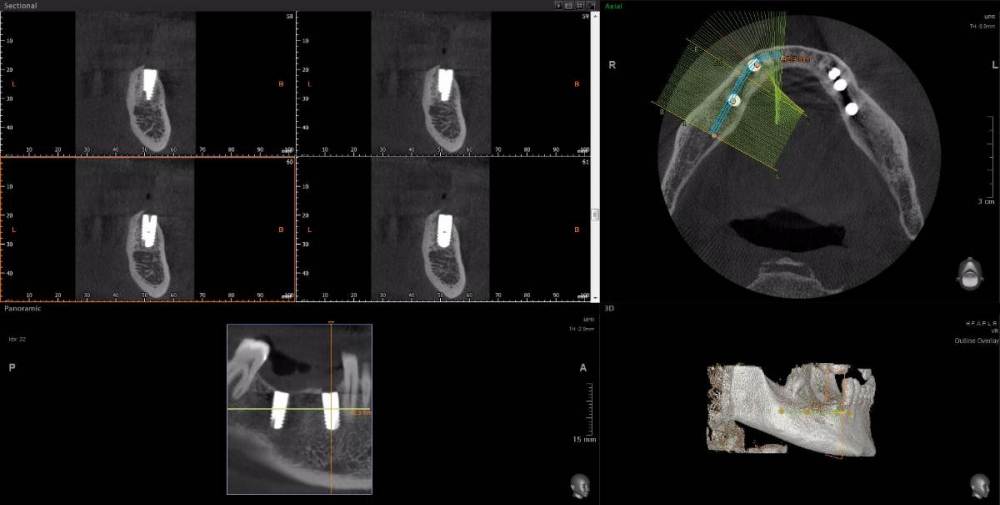

m-art-a23 Опубликовано 21 апреля, 2021 Поделиться Опубликовано 21 апреля, 2021 Здравствуйте. Два дня назад мужу установили 5 имплантов Ankylos на нижнюю челюсть (2+3). Спустя 30-40 мин после операции появилась сильная острая боль, которая не уменьшается по настоящее время. Боль похожа по ощущениям на пульпитную, не снимается никакими НПВС, кроме кеторолака. А/б, А/гистаминные, холод местно, хлоргексидин - все рекомендации выполнялись. На осмотре врачом не обнаружено следов воспаления, КТ сделал - без особенностей. Что может служить причиной такой боли, сколько она может длиться и что делать в данной ситуации? Врач-имплантолог ничего внятного не предложил. Ссылка на КТhttps://cloud.mail.ru/public/EvKn/ULqxLy6BD Ссылка на комментарий

wladdX Опубликовано 21 апреля, 2021 Поделиться Опубликовано 21 апреля, 2021 (изменено) Вы не указали локализацию болей, слева или справа? Левая сторона Справа Изменено 21 апреля, 2021 пользователем wladdX 1 Ссылка на комментарий

red_butler Опубликовано 22 апреля, 2021 Поделиться Опубликовано 22 апреля, 2021 7 минут назад, m-art-a23 сказал: Нет, не один. Но он лучший. Скажите пожалуйста, что служит причиной боли, по-Вашему? Неужели все импланты нужно убирать только по Кт трудно судить, но есть вопросы по позиционированию имплантов... боль может быть вызвана перегревом кости во время формирования ложа импланта, но в этом случае она появляется примерно с третьего дня. Так же боль может вызывать гиперкомпрессия импланта, и может болеть кость если ее придавили формирователем десны. Я бы обсудил с хирургом удаление среднего импланта слева 1 Ссылка на комментарий

Irouil Опубликовано 22 апреля, 2021 Поделиться Опубликовано 22 апреля, 2021 Я бы рекомендовал удаление среднего импланта слева, независимо от наличия/отсутствия болевых ощущений боль может быть признаком каких-то описанных моим коллегой процессов, а может ничего кроме самой боли не означать (менее вероятно, но и такое бывает). Если удаление упомянутого импланта поможет против болевого синдрома - это win-win если хирург не видит необходимости удаления импланта, я бы рекомендовал сходить на осмотр к ортопеду, который будет в будущем эти импланты протезировать. Возможно у него найдутся весомые аргументы для коллеги 3 Ссылка на комментарий

Irouil Опубликовано 22 апреля, 2021 Поделиться Опубликовано 22 апреля, 2021 (изменено) 1 час назад, m-art-a23 сказал: Благогдарю за совет. Если Вам не трудно, объясните пожалуйста, что не так со средним имплантом. Описанные процессы, если таковые имеют место быть, должны постепенно прийти в норму? Другими словами, сколько еще нужно времени, чтобы окончательно принять решение об удалении импланта (имплантов)? Сегодня третьи сутки после установки. Боль сохраняется. Средний имплант расположен чрезвычайно близко к соседнему, расположенному кпереди от него. С очень большой долей вероятности это может привести к значительной резорбции (убыли) костной ткани между ними, что для любых имплантов очень вредно, а для конкретно Анкилосов - губительно из-за особенностей их протезирования. Если неблаготворные процессы (компрессионный или термический некроз) присутствуют, то импланты просто не интегрируются (не приживутся) - те, что зашиты не выдержат нагрузки при раскрытии, а тот, на котором стоит ФДМ - расшатается через 2-3 недели. Это не призыв проверять его стабильность языком, сейчас его лишний раз лучше не трогать. В норме после имплантации боли держатся 1-2 дня, если все не очень хорошо - держатся 2-3 недели, но даже в таком случае имплант может интегрироваться, поэтому решение об его удалении в таком случае должно, по моему убеждению, быть совместным между врачом и пациентом, и приниматься в индивидуальном порядке Изменено 22 апреля, 2021 пользователем Irouil Ссылка на комментарий